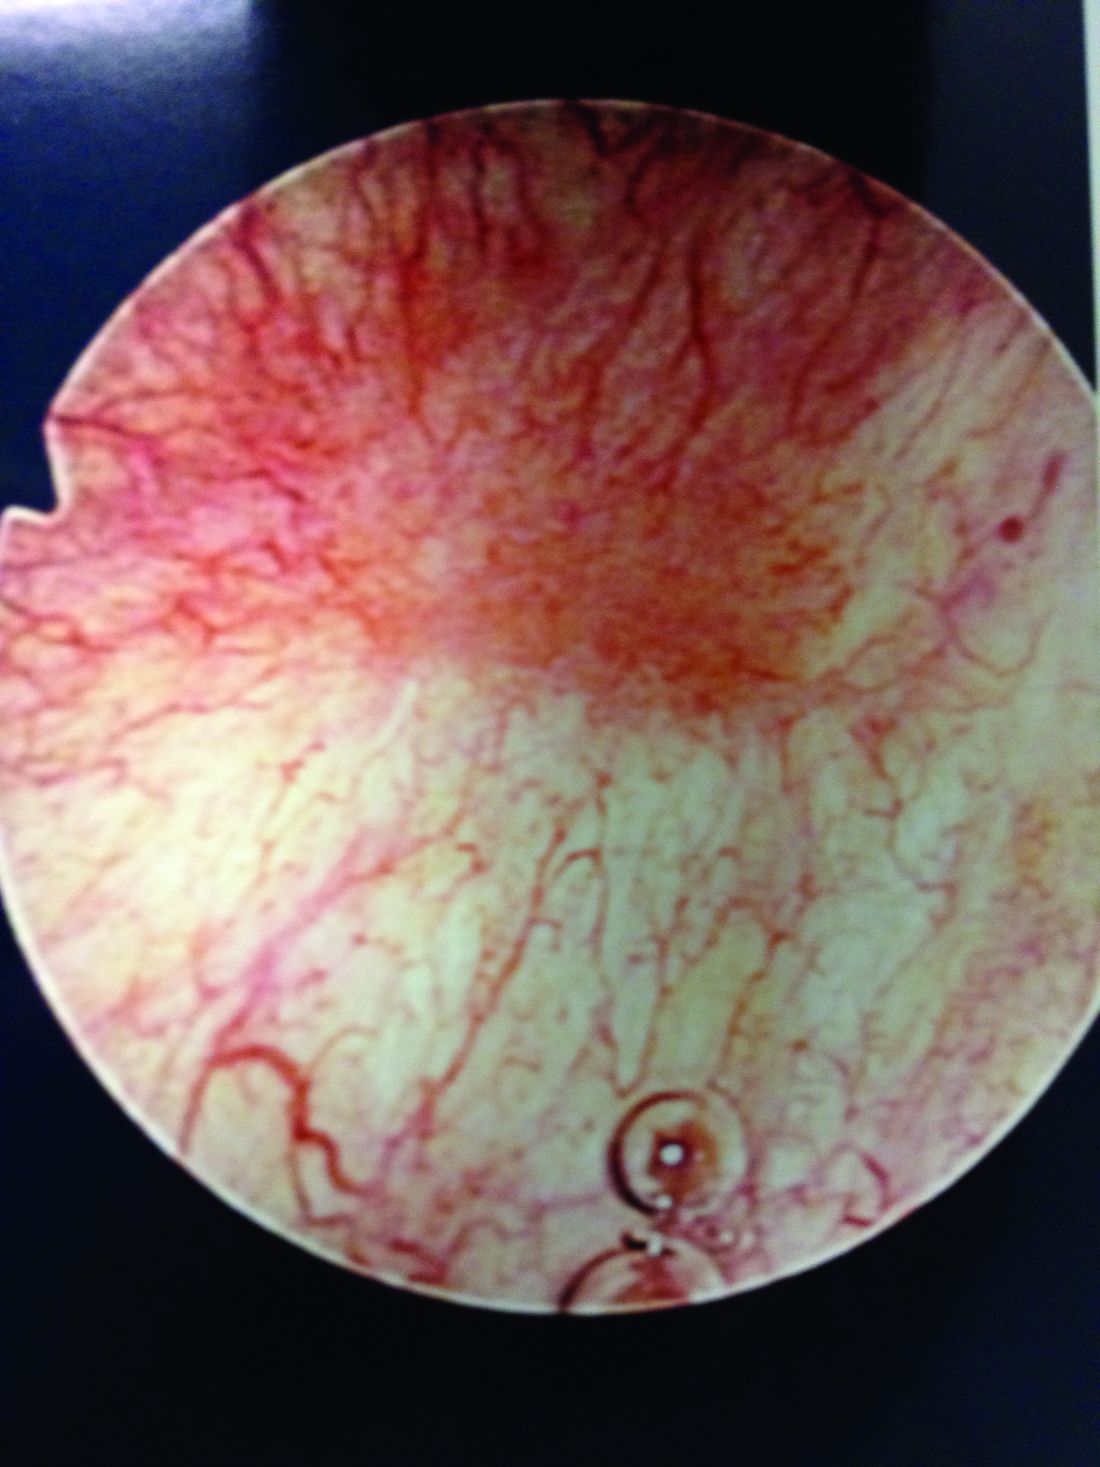

From ar.inspiredpencil.com

Cystoscopy of Interstitial Cystitis YouTube Bromelain Interstitial Cystitis Symptoms of ic may be different among people. You may also feel pain in the groin and pelvic floor muscles. Interstitial cystitis/bladder pain syndrome (ic/bps) primarily affects women, with unremarkable findings on. Oral bioflavonoid therapy utilizing quercetin recently. The treatment uses an electric current to create heat. Research has shown that quercetin may have several beneficial effects for people with. Bromelain Interstitial Cystitis.